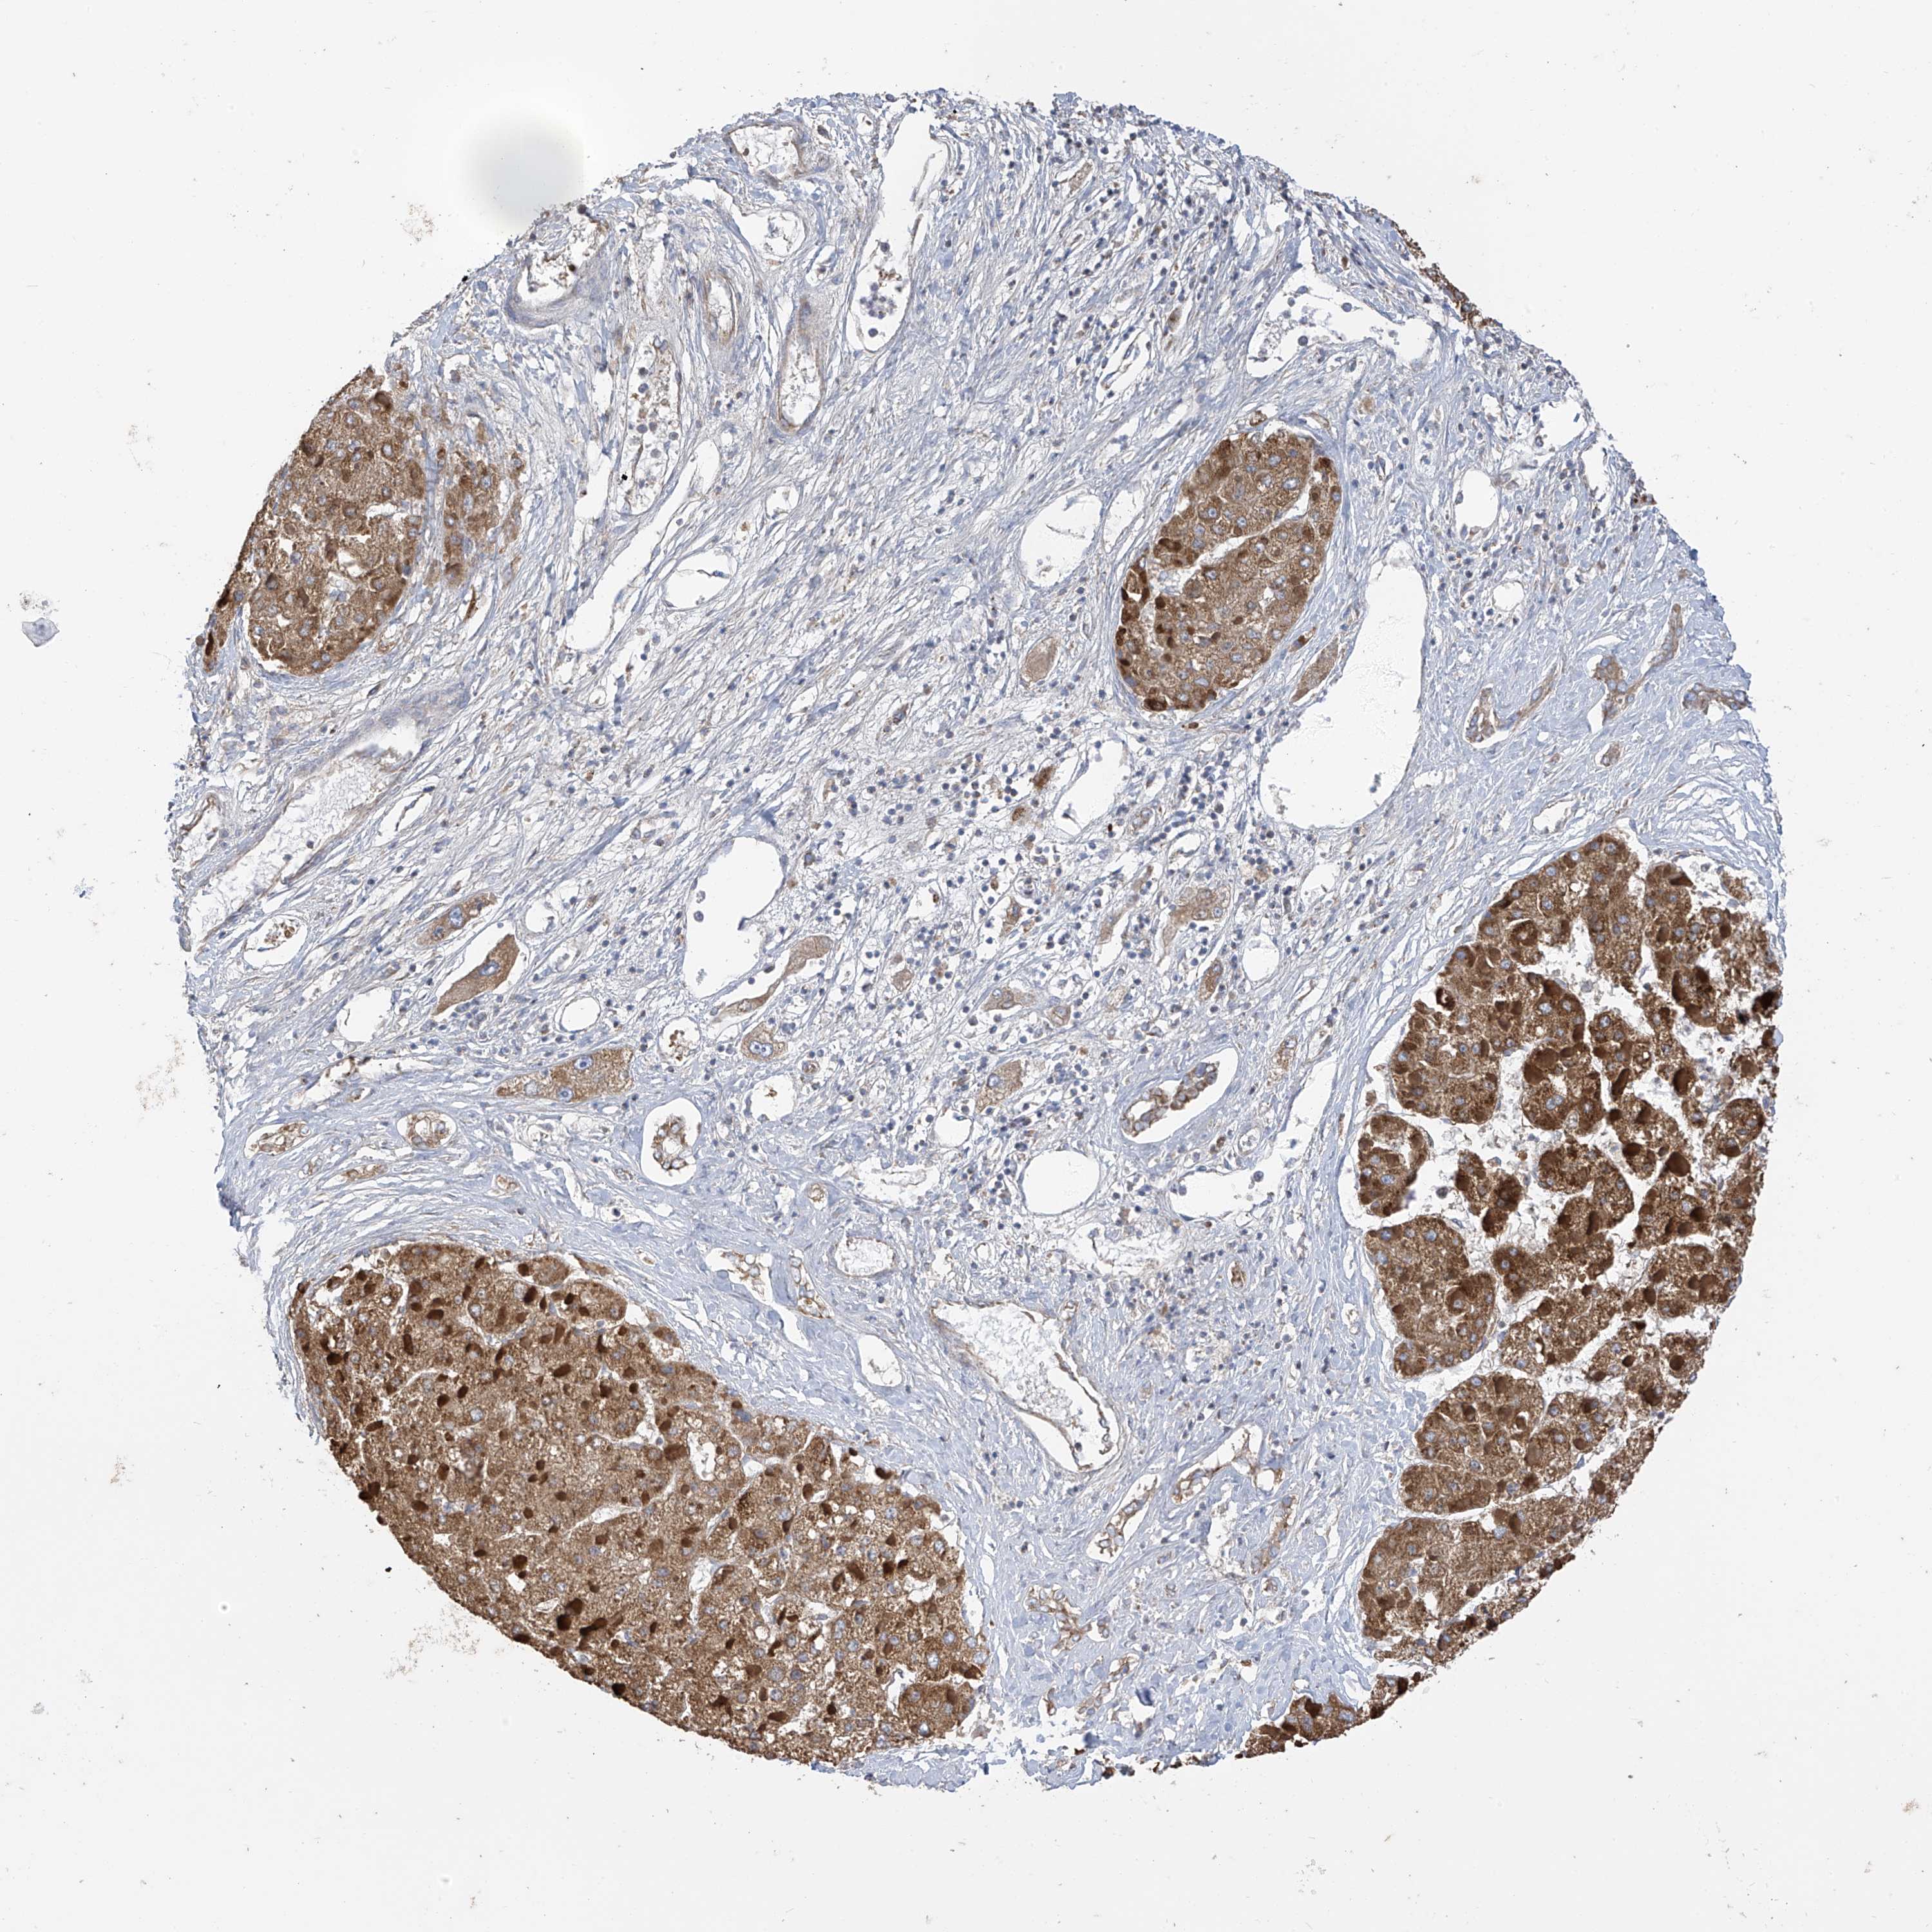

LIVER CANCER - Protein expressioni

A mouse-over function shows sample information and annotation data. Click on an image to view it in a full screen mode. Samples can be filtered based on level of antibody staining by selecting one or several of the following categories: high, medium, low and not detected. The assay and annotation is described here.

Note that samples used for immunohistochemistry by the Human Protein Atlas do not correspond to samples in the TCGA dataset.

Antibody stainingi

Antibody staining in the annotated cell types in the current human tissue is reported as not detected, low, medium, or high, based on conventional immunohistochemistry profiling in selected tissues. This score is based on the combination of the staining intensity and fraction of stained cells.

Each image is clickable and will lead to virtual microscopy that enables deeper exploration of all samples and also displays staining intensity scores, fraction scores and subcellular localization as well as patient and tissue information for each sample.

Antibody HPA034602

Antibody HPA034603

Antibody CAB033424

Staining

High

Medium

Low

Not detected

Intensity

Strong

Moderate

Weak

Negative

Quantity

>75%

75%-25%

<25%

None

Location

Nuclear

Cytoplasmic/membranous

Cytoplasmic/membranous,nuclear

Cholangiocarcinoma

Carcinoma, Hepatocellular, NOS